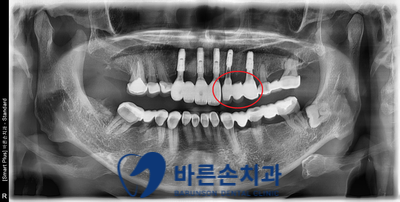

3개월 후,

최종 보철물이 다 올라간 사진입니다.

잇몸 라인에 맞게, 주변치아와 잘 조화되도록

자연스러운 보철물을 세팅하였습니다.